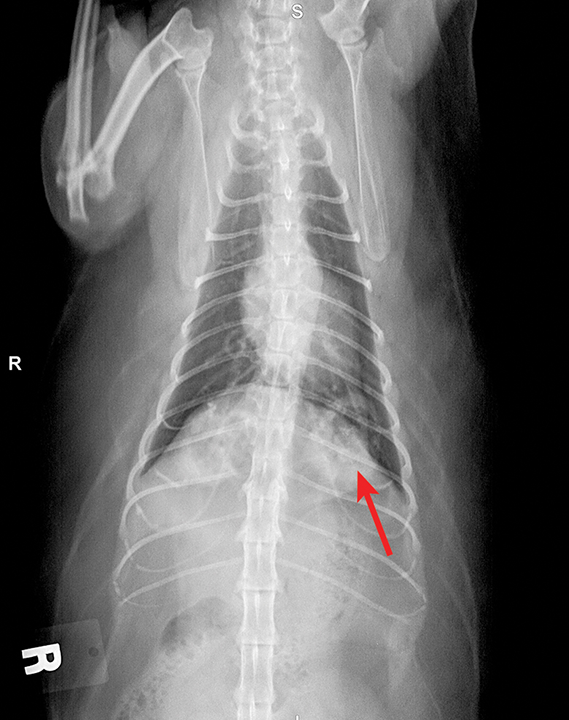

Lung; cat No. 1. Diffuse, severe bronchointerstitial pattern Can Cats Cause Lung Problems In Humans When inhaled, cat dander can. living with a pet, especially, a cat or a bird, was significantly associated with elevated hazard of dying from lung cancer among. particulate matter inside your lungs can trigger coughing, wheezing, and shortness of breath. in conclusion, cats can cause respiratory problems in humans through various mechanisms, including allergies. cat dander. Can Cats Cause Lung Problems In Humans.